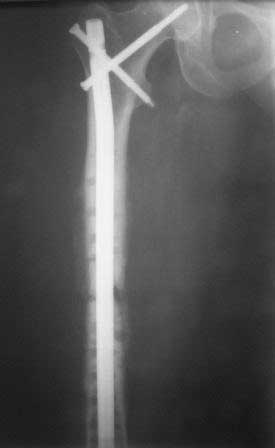

Результат нашего лечения:  Произведено удаление пластины МIPO. Интрамедуллярный остеосинтез с рассверливанием канала. На 2-е сутки после операции больная передвигается при помощи костылей, с полной нагрузкой на оперированную конечность, болей в области перелома нет.

Фотографии в приложении.